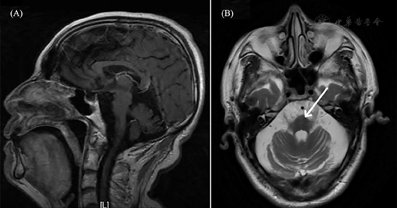

入院后先后给予哌拉西林他唑巴坦、莫西沙星抗感染治疗,复查胸部CT感染明显改善,尿培养转阴后体温仍持续增高。监测降钙素原阴性。完善结核菌素试验、结核感染T淋巴细胞检测、结核抗体、真菌检查、呼吸道病毒[嗜肺军团菌、肺炎支原体免疫球蛋白M(immunoglobulin M, IGM)、肺炎衣原体IGM、腺病毒抗体IGM、呼吸道合胞病毒、流感病毒A型、流感病毒B型、副流感病毒抗体IGM]、一组病原微生物包括弓形虫、其他感染性病原体、风疹病毒、巨细胞病毒、单纯疱疹病毒十项检查(弓形体抗体IGM/IgG、风疹病毒抗体IGM/IgG、巨细胞病毒抗体IGM/IgG、单纯疱疹病毒抗体I型IGM/IgG、单纯疱疹病毒抗体II型IGM/IgG)、EB病毒、巨细胞病毒等均阴性。多次复查血、痰、尿细菌及真菌培养均为阴性。脑脊液常规、生化检查未见显著异常,细菌及真菌培养涂片及培养亦为阴性。追问病史,补诉1年余来无汗,体温随环境温度变化。结合患者头颅磁共振成像(MRI)可见脑萎缩、桥脑+字征等表现(图1)。查阅患者既往外院病历,既往立卧位试验示卧位血压129/79 mmHg、心率68次/min,坐位血压99/74 mmHg、心率92次/min。尿流动力学检查:膀胱逼尿肌收缩力弱,尿潴留,充盈性尿失禁,头颅MRI:脑萎缩改变,桥脑可见+字征,肌电图:双下肢颈神经H反射,右下肢F波未见异常,双上肢皮肤交感反应(SSR)潜伏期正常,波幅明显降低,双下肢SSR未引出肯定波形;双下肢体感诱发电位:双下肢H8潜伏期延长,右侧皮层波形分化不良。据Gilman等[1]提出的诊断标准,符合多系统萎缩C型(小脑共济失调为主型)。经影像科、神经内科会诊,考虑多系统萎缩累及下丘脑,导致体温调节中枢受损。调节室内温度后患者体温渐回降至37.5℃,入院第8日关闭室内暖气后体温进一步降至37℃(图2A)。

注:(A)矢状位T1加权成像中脑、脑桥、延髓以及下丘脑萎缩;(B)轴位T2加权成像脑桥"十字征"(箭头所指)、T2加权像四脑室扩大